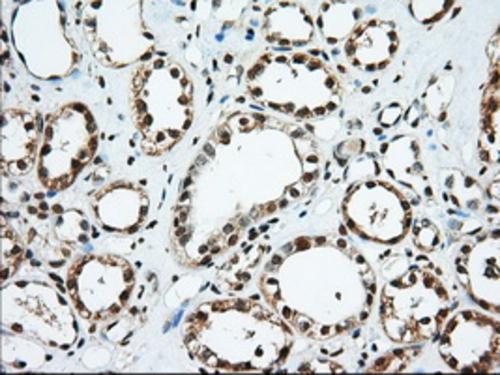

Immunohistochemical staining of paraffin-embedded Human Kidney tissue within the normal limits using anti-EIF2S1 mouse monoclonal antibody. (Heat-induced epitope retrieval by 10mM citric buffer, pH6.0, 100°C for 10min, BD-PE2158, Dilution 1:50)